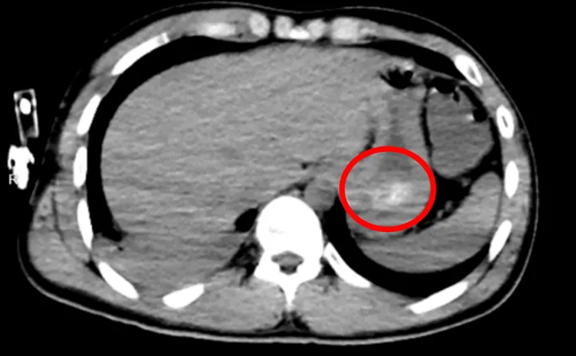

Chụp CT đã cho thấy nguyên nhân: trong dạ dày của anh tồn tại một khối lớn kết dính từ các viên thuốc, gọi là “bezoar thuốc” (khối thuốc đông kết). Không chỉ vậy, anh còn bị viêm phổi hít do nôn trớ trong lúc ý thức kém, khiến tình trạng càng nguy kịch.

Qua nội soi, bác sĩ phát hiện toàn bộ dạ dày bị chặn bởi một khối thuốc lớn màu vàng, dễ vỡ. Quá trình làm sạch kéo dài 43 phút, với hàng chục lần rửa và gắp, cuối cùng đã loại bỏ hoàn toàn “quả bom độc” này khỏi cơ thể.